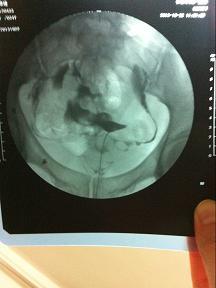

34岁,没流过产也没怀过孕,月经周期40天左右 造影的诊断结果为:两侧输卵管上举,伴通而不畅 请问 怎么样才能治好,中医可以治好吗? 点击展开 匿名用户 2013-11-10 09:40 为您推荐: 其他回答 病情分析: 你好,中医效果不大的。 指导意见: 可以考虑腹腔镜手术来治疗,术后注意不可过早恢复同房,及时复查。 独水凡_xjeq 2013-11-10 10:08 相关问题 想要二胎,两年未孕,月经不调去医院检查做输卵管造影是通而极不畅,吃了两个月的中药,又做了输卵管通液 卵泡成熟用了药和促排卵针还是没排,输卵管通,月经周期正常…怎么治,要吃药打针多久才有改善? 女性输卵管不通,月经周期正常,在此情况下用药店购买的排卵测试纸,能测试出女性是否正常排卵吗?